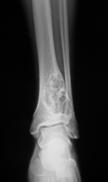

Basit Kemik Kisti

Basit kemik kisti; unikameral kemik kisti veya soliter kemik kisti olarak da bilinir. Kistin etrafı fibrotik doku ile çevrili ve içerisi sıvı doludur. Hastaların %80’i onlu ve yirmili yaşlardadır. Humerus (kol kemiği), femur (uyluk kemiği) üst uçlarında, erişkinde ise kalkaneus ve iliumda (leğen kemiği) görülür.İskelet sistemi büyümesi tamamlandığında genellikle kendiliğinden iyileşir.

Basit kemik kistininvenöz sirkülasyon bozukluğu sonucu geliştiği düşünülmektedir. Venöz kan akımındaki blokaj kemiğin rezorpsiyonuna neden olur. Basit kemik kisti uzun kemiklerin metafizer bölgelerinde gelişir. Yaşamın ilk dekatında daha agresifdir. Genelde asemptomatiktir. Orta derece ağrı, lokal hassasiyet ve şişlik mevcut ise patolojik kırık olduğunu düşündürür. Bulgular olmadan tesadüfen de saptanabilir.

Düz grafi teşhiste çok değerlidir. Düşen yaprak görüntüsü basit kemik kistine özgüdür. Kist kemiğin metafizer bölgesinde meduller boşlukta oluşur ve diafize doğru gelişir. Lezyon balona benzer. Lezyonların %15’i tedavi yapılmadan kendiliğinden iyileşir. Anevrizmal kemik kisti ve fibröz displazi ile karışabilir.